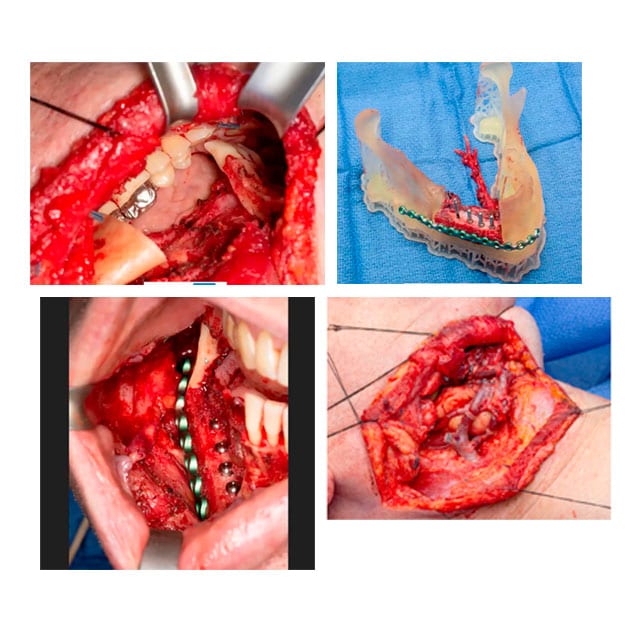

Free-flap reconstruction

The images show a resected area prior to reconstruction, a preassembly tray with fibula free flap, titanium plate and implants. The completed free-flap reconstruction and nerve graft and neck access show completed microvascular connection.

Survival of the free flap depends on connecting the blood vessels and keeping them open and flowing. Using a surgical microscope, Dr. Ettinger connected the blood vessels in the flap to those in the neck, allowing blood to flow into the flap via the arteries and out of the flap via the veins. From start to finish, these surgeries typically take about 4 to 6 hours.